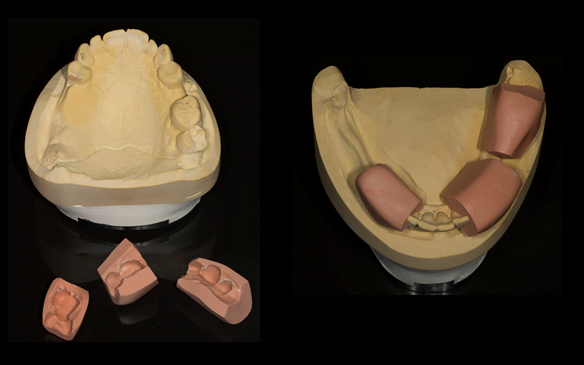

This newsletter describes in step by step detail Angela's transition through immediate partial dentures to crown supported definitive metal based dentures.

The clinical situation and treatment process is shown in detail below with photographs. I (Finlay Sutton) provided the clinical work and Rowan Garstang provided the technical work.